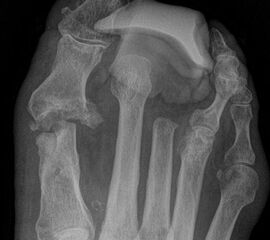

Wir bevorzugen die Amputation im Mittelfußknochen gegenüber der Exartikulation im MTP Gelenk (Abb. 10): Ein Ulkus an dem Metatarsale I Stumpf ist durch stützende Einlage zu verhindern.

Tennisschlägerartige Umschneidung der Großzehe (Abb. 11). Das Metatarsale wird so osteotomiert, dass an der Medial- und Plantarseite keine Knochenkanten verbleiben (Abb. 12).